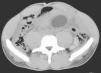

El paciente acudió a urgencias con clínica de dolor abdominal intenso de 24h de evolución y fiebre. A la inspección general impresiona de gravedad, y en la exploración presenta dolor abdominal difuso, más intenso en hipogastrio y fosa ilíaca derecha (FID), con defensa involuntaria y signos de irritación peritoneal. Los resultados de la analítica de urgencias se encuentran dentro de la normalidad. En la radiografía de abdomen no se aprecian signos de obstrucción o neumoperitoneo. En la tomografía computarizada (TC) se observa abundante líquido libre subhepático, en el canal paracólico derecho y FID. No se visualiza apéndice ni gas ectópico. Informan de una masa quística de 5cm de diámetro, de paredes finas y densidad grasa. Se localiza entre asas yeyunales y es compatible con linfangioma quístico, que no parece estar complicado (fig. 1).